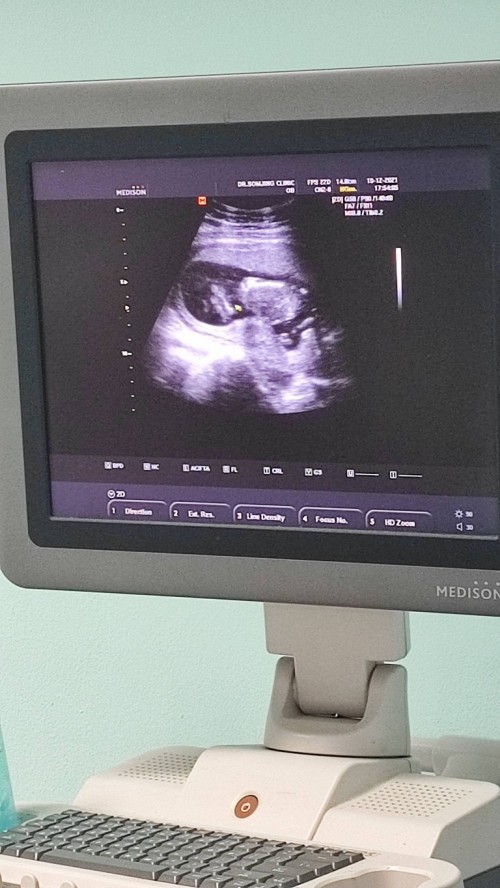

ซาวด์ตอน27วีคค่ะ ปัจจุบัน36วีค ลูกชาย